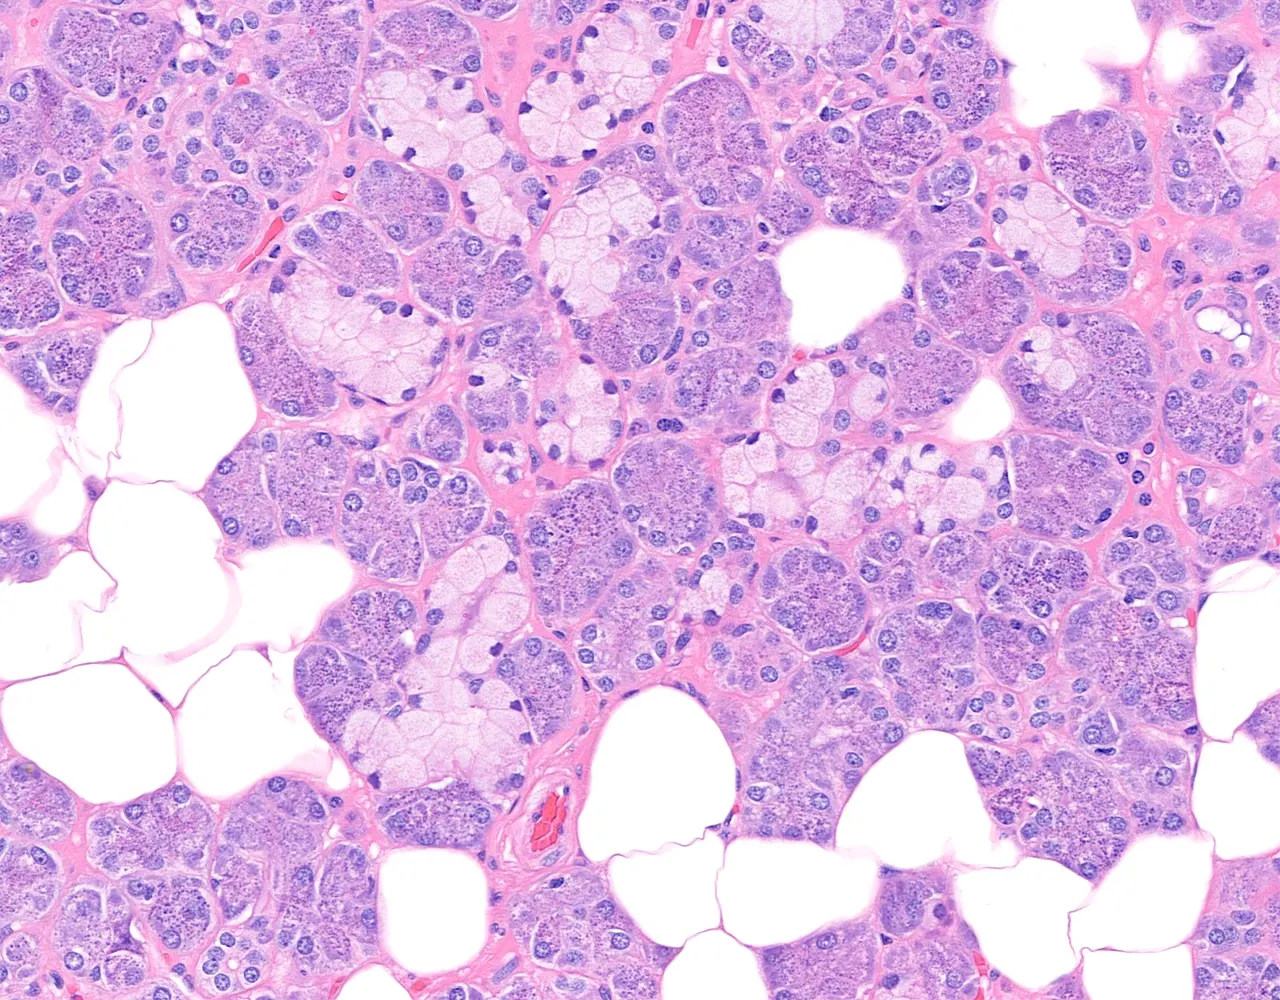

- Microscopically, the functional structure of a salivary gland consists of secretory acini and a duct system.